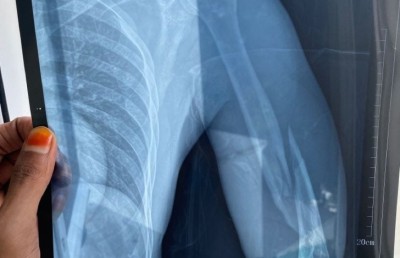

ފަތޯގެ އަތުގެ އެކްސްރޭއިން ފެންނަ ގޮތުގައި އޭނާގެ ވައަތުގެ ކޮނޑުހުޅާއި އުޅަނބޮއްޓާ ދެމެދުން ވަނީ ބިންދައިގެން ގޮސްފަ އެވެ. އެ އަތް އޮޕަރޭޝަންކޮށް ބޮލްޓު އަޅަން ޖެހިފައިވާ ކަމަށް ޑޮކްޓަރުންނާ ހަވާލާދީ އޭނާ ބުންޏެވެ.